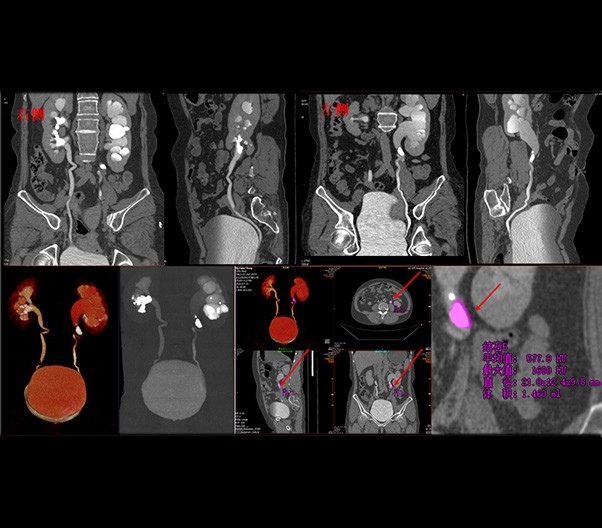

臨床畫廊